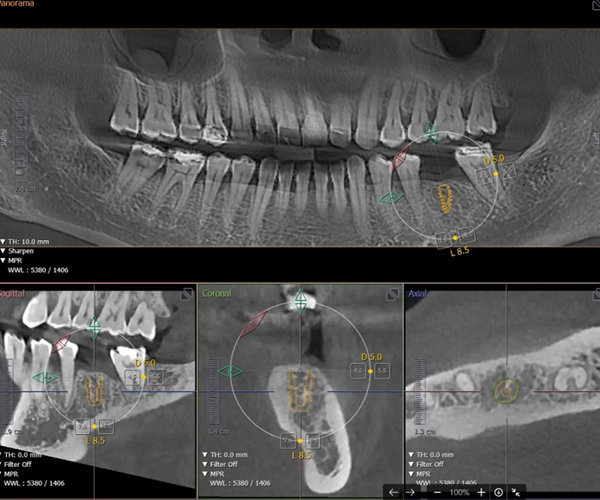

3D 수술 가이드를 통한

오차 없는 초정밀 수술

네비게이션 디지털 임플란트

3D CBCT와 최신 디지털 스캐너를 이용해 채득한 구강 데이터를 기반으로 3D 모의수술 후 맞춤 제작된 수술 가이드를 사용해 미리 계획된 위치에 오차 없는 정확한 식립이 가능하기 때문에 고난이도 임플란트 케이스도 적용 가능하며, 최소침습으로 수술 시간이 짧고 체력적으로 부담이 적습니다.

3D CT&스캐너 디지털 정밀 진단

• 일반 임플란트 치아 상태 및 신경의 위치를 2D(평면)으로만 확인이 가능해 정확한 진단이 어려울 수 있음

• 3D CT를 통한 컴퓨터 분석 현재 턱 뼈와 잇몸의 상태를 3차원 입체 영상으로 확인이 가능해 정밀 진단에 따른 오차 없는 수술이 가능